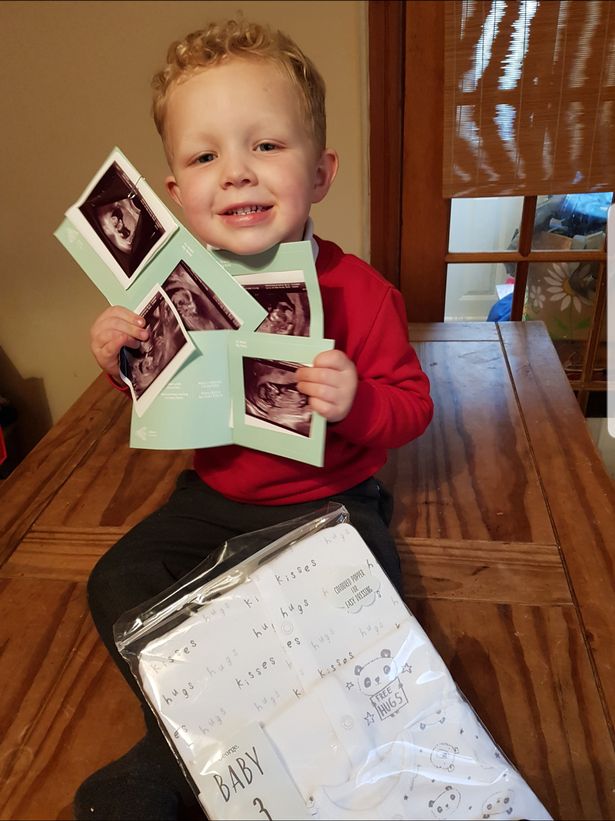

Vì cậu con trai Jacob (4 tuổi) đã lớn nên vợ chồng chị Katie Craw (26 tuổi), đến từ Pentre Ma Bachelor, Wales (Anh), quyết định sẽ sinh thêm một đứa con nữa cho vui cửa vui nhà. Và điều kỳ diệu đã xảy ra khi sang tháng thứ 2 kể từ lúc "thả", chị Katie cấn bầu. Cả gia đình vui mừng và hồi hộp vì không biết thành viên thứ 4 này là em trai hay em gái.

Bà mẹ 4 con kể: "Dù chỉ mới ở tuần thứ 12, nhưng tôi đã mặc vừa những bộ đồ bầu cũ của mình. Tôi chợt nhận ra rằng có lẽ tôi sẽ có hơn 1 đứa con. Trong vòng 5 giây sau khi bác sĩ đặt máy dò lên bụng, cô ấy liền bảo tôi hít một hơi thật sâu. Lúc đó, tim tôi rớt 1 nhịp vì lo sợ có điều gì đó xấu xảy ra. Nhưng rồi… cô ấy bảo 'tôi thấy có 3 nhịp tim'. Tôi sững sờ.

Jacob vui vẻ với những tấm hình siêu âm của các em.